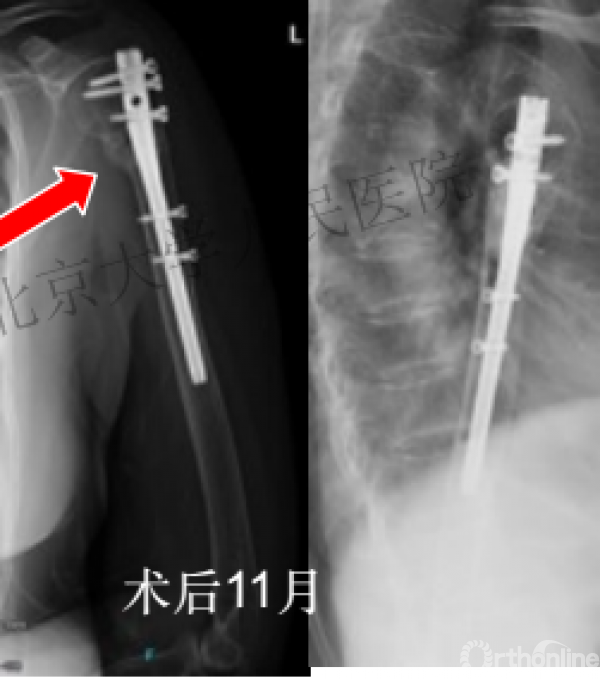

复位良好的标准:颈干角:135°,大结节与肱骨头距离:8mm

术后3月随访:继发性颈干角变小22°(5-82),肱骨头内翻,达46%

严重影响了患者的生活质量

可否有更好的进钉和复位的更好帮助办法?

进钉更完美——我们的帮助